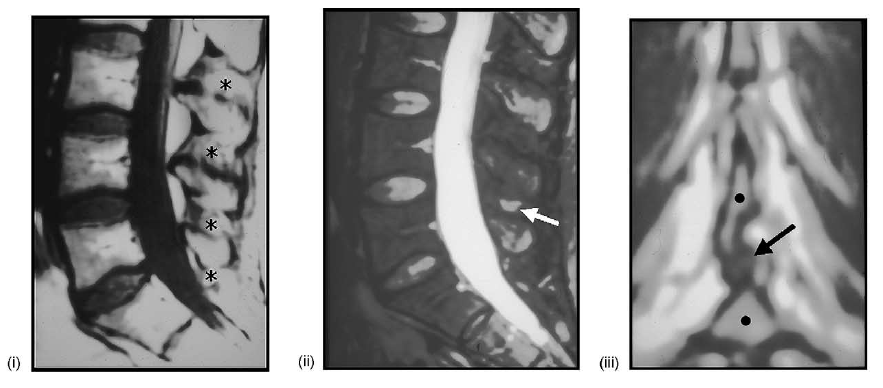

(i) midline sagittal T1-weighted MRI showing hyperintensity of the interspinous ligaments at multiple levels (asterisks). (ii) Midline sagittal T2-weighted, fat-suppressed MRI showing isolated hyperintensity of the L5-S1 interspinous space (arrow) indicating degeneration and possible cystic alteration of the interspinous ligament (compare with (A)). (iii) Coronal T1-weighted MRI showing the rounded appearance of the interspinous ligament (arrow), between the spinous processes of L5-S1 (dots).

(iv) Coronal T2-weighted, fat-suppressed MRI showing again the apparent cystic degeneration of the interspinous ligament situated between the spinous processes of L4 and L5 (dots; compare with iv). (v) Axial T1-weighted MRI showing multiple rounded paraspinous soft tissue structures (arrows); also note the spinous process of L5 (black dot) and the redundant-hypertrophic inter-supraspinous ligament(s) (white dot) (compare with (D)). (vi) Axial T2-weighted, fat-suppressed MRI showing the hyperintense nature of the paraspinous cysts (arrows; same patient in (E) v–vi).

(vii) Sagittal T2-weighted, fat-suppressed MRI showing two interspinous cysts extending into the posterior aspect of the central spinal canal at L3-L4 and L4-L5 (arrows; compare with (D)). (viii) Midline sagittal T1-weighted MRI showing multilevel posterior redundancy-hypertrophy of the supraspinous ligament (arrows; compare with (B)).